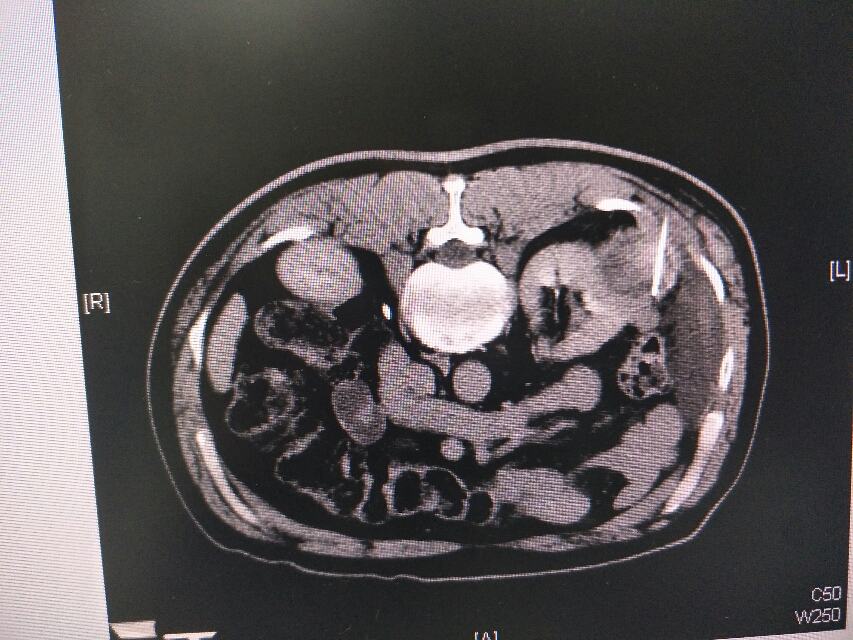

肾癌化疗及靶向治疗效果差,后予射频消融手术